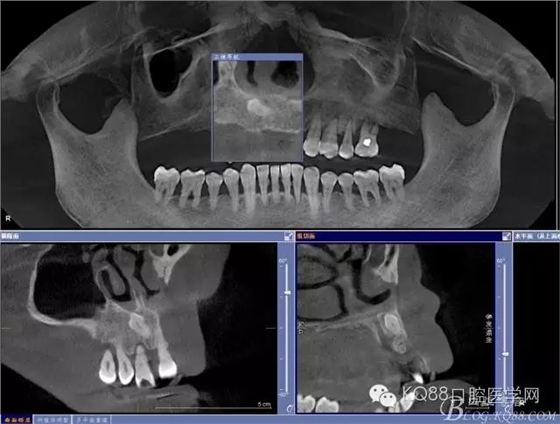

檢查:11、12、13Ⅲ度松動,牙齦退縮,根面暴露,14、15、16、17缺失,余牙不同程度牙齦退縮。

輔助檢查:ct示骨密度良好,11 12區(qū)域骨下有一水平向埋伏牙,15 16區(qū)域骨高度2.5-3mm,骨寬度6-9mm。